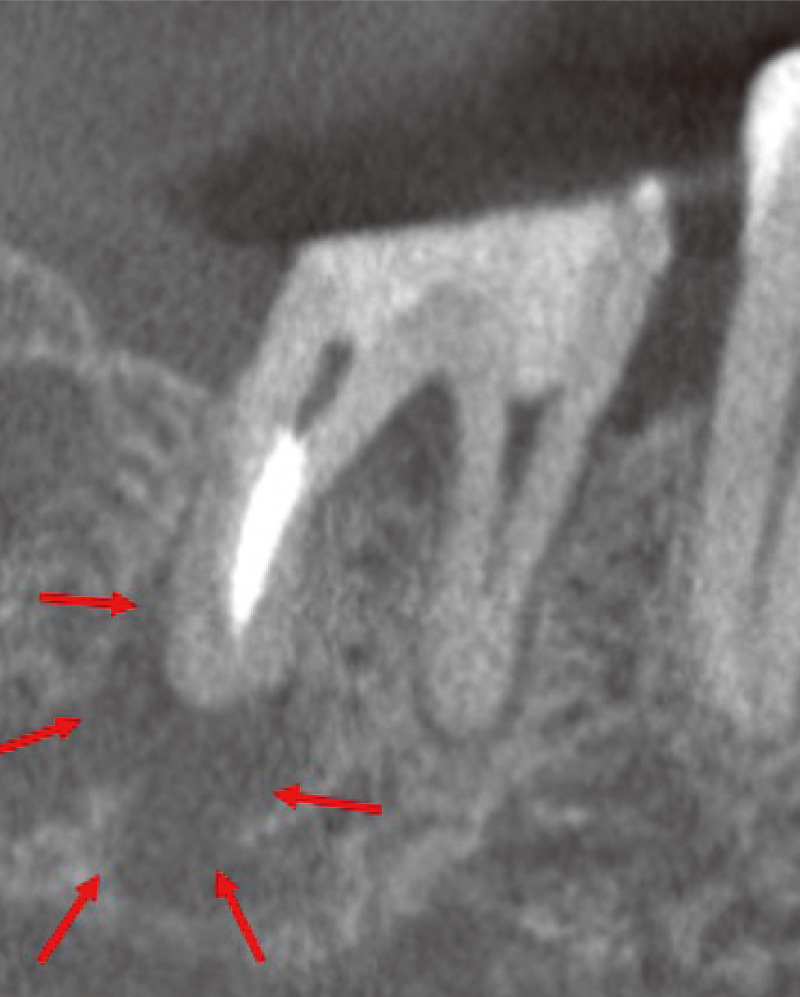

症例紹介③ 根尖孔外ガッタパーチャを除去した症例 加藤 真悟先生

![[写真] 46歳男性 ンタルX線にてオーバー根充を認める](/academic/dentalmagazine/wp-content/uploads/sites/2/2025/11/195-3_photo13.jpg)

46歳男性。主訴は₇の咬合痛であった。デンタルX線にてオーバー根充を認める。 -

![[写真] 治療前のCBCT画像](/academic/dentalmagazine/wp-content/uploads/sites/2/2025/11/195-3_photo14.jpg)

治療前のCBCT画像。根尖孔外に突き出した根管充填材を認める樋状根であった。(Veraviewepocs 3Dfにて撮影) -